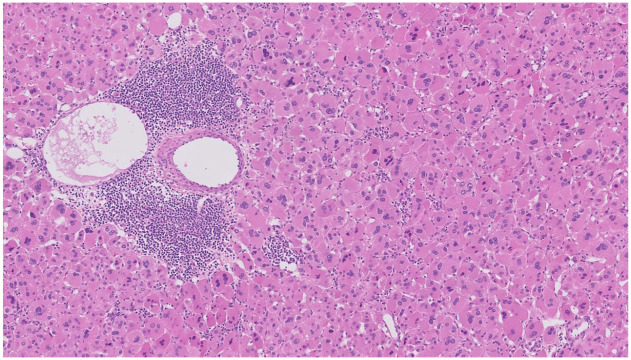

Background: Oncocytic adrenocortical neoplasms (OANs) are extremely rare adrenal tumors whose diagnosis is challenging. This study aimed to identify risk factors for predicting poor prognosis in patients with OAN of uncertain malignant potential (OANUMP) and oncocytoma, OAN subtypes, and to evaluate the diagnostic utility of the current Lin-Weiss-Bisceglia (LWB) criteria.

Methods: We retrospectively reviewed 14 patients diagnosed with OANUMP or oncocytoma after adrenalectomy from February 2002 to May 2022. Patients re-classified as oncocytic adrenocortical carcinoma by the LWB criteria were excluded. We compared the clinicopathological and radiological features between patients with and without recurrence.

Results: Among the 14 patients, recurrence occurred in 3 (21%; 2 (67%) and 1 (33%) patients with OANUMP and oncocytoma, respectively). The proportion of patients with necrosis (66.7% vs 9.1%, p = 0.093), a Helsinki score >5 (66.7% vs 9.1%, p = 0.093), and malignancy by the reticulin algorithm (66.7% vs 9.1%, p = 0.093) were higher in the recurrence group than in the no-recurrence group but were not statistically significant. The percentages of patients with an indeterminate pathological resection margin (100% vs 63.6%, p = 0.192) tended to be higher in the recurrence group than in the no-recurrence group. Of the three patients with recurrence, two had tumor necrosis on the final pathology and were classified as malignant by the reticulin algorithm. One patient diagnosed as OANUMP by the LWB criteria had tumor necrosis and was classified as malignant by the reticulin algorithm and Helsinki scoring system.

Conclusion: Necrosis was associated with the recurrence of disease in patients with OANUMP according to the LWB criteria. The absence of necrosis as a major criterion in the current LWB criteria highlights its potential limitation in accurately assessing disease aggressiveness in OANs.